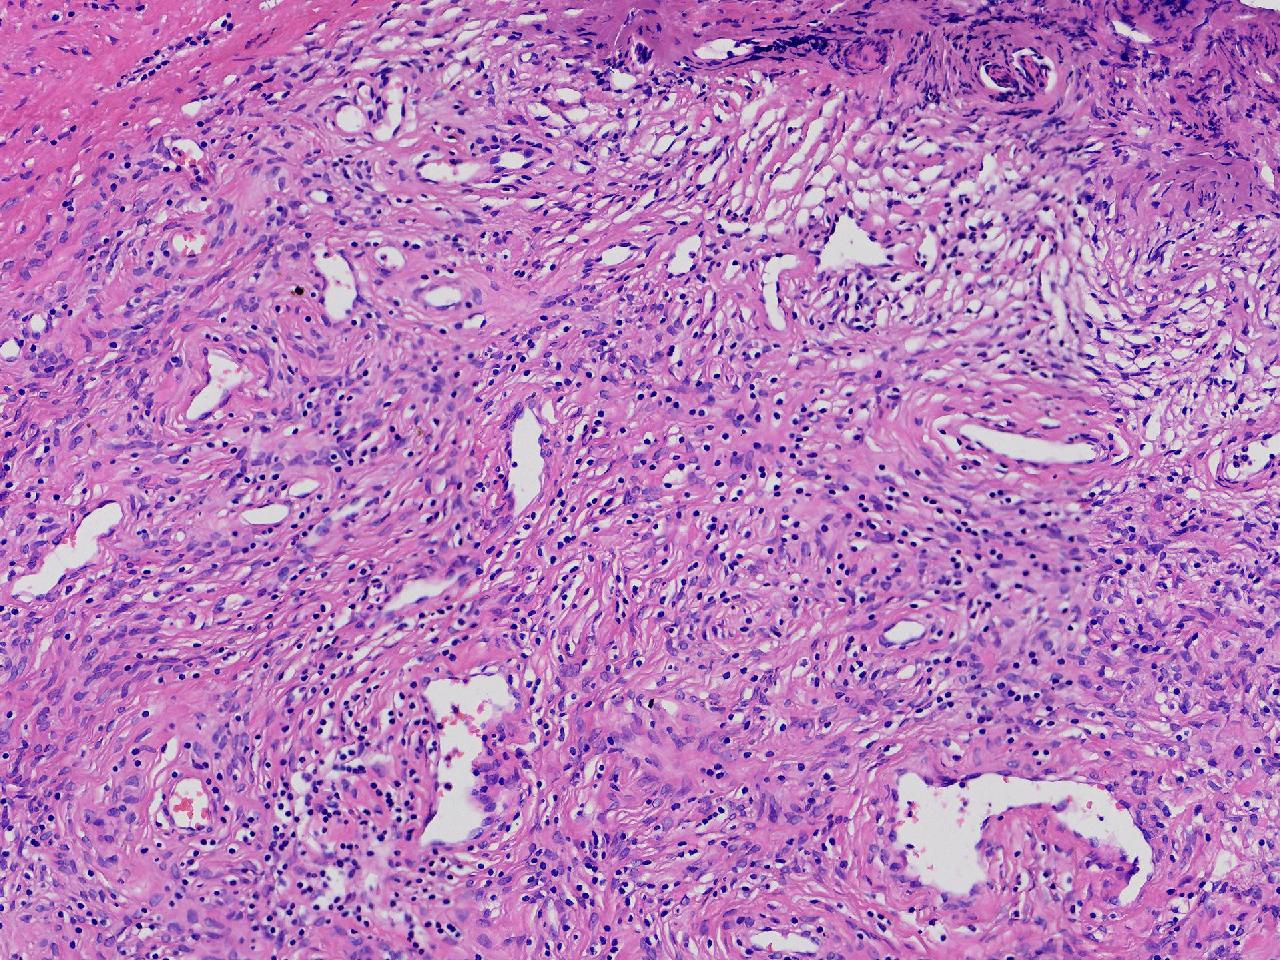

这些腺体有问题吗?

男,77岁,排尿困难2年,尿潴留3天。

标本名称

电切前列腺组织

图2